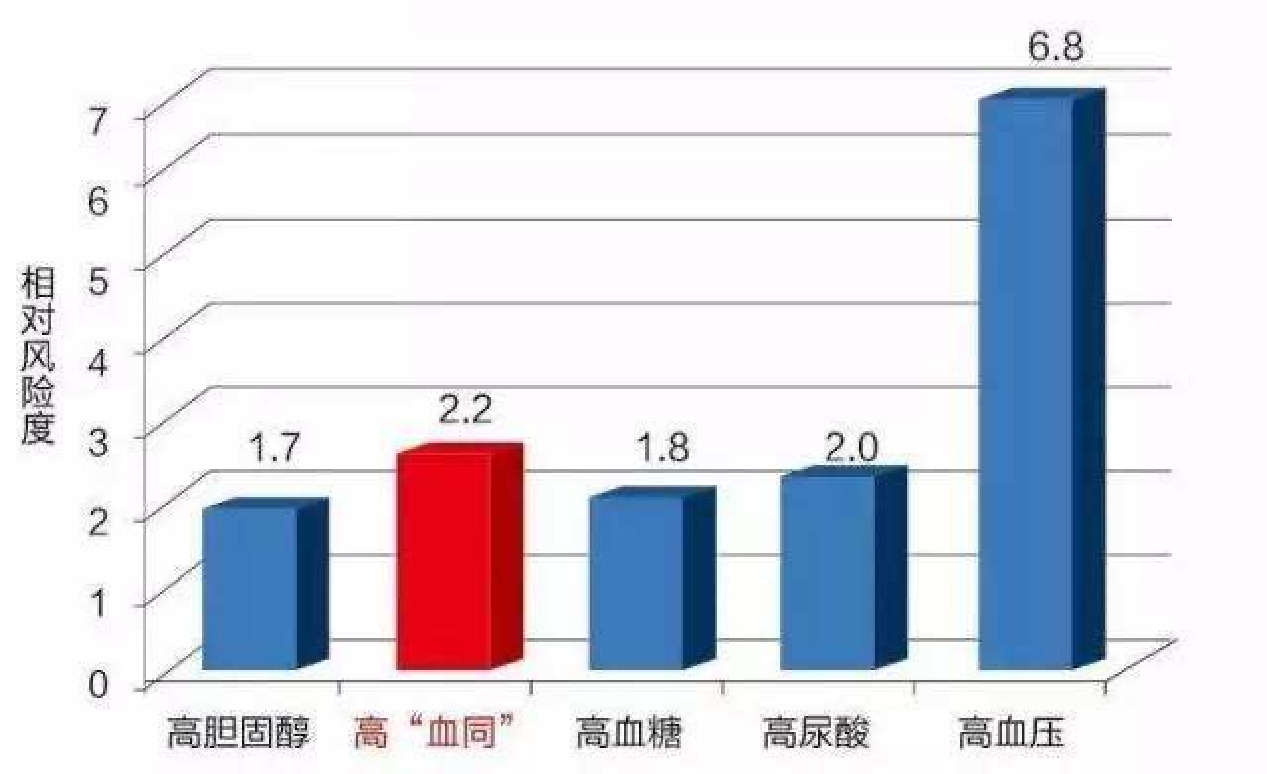

心脑血管五大独立危险因素

高同型半胱氨酸血症(高血同)在这五大独立危险因素中的相对危险度排名第二。